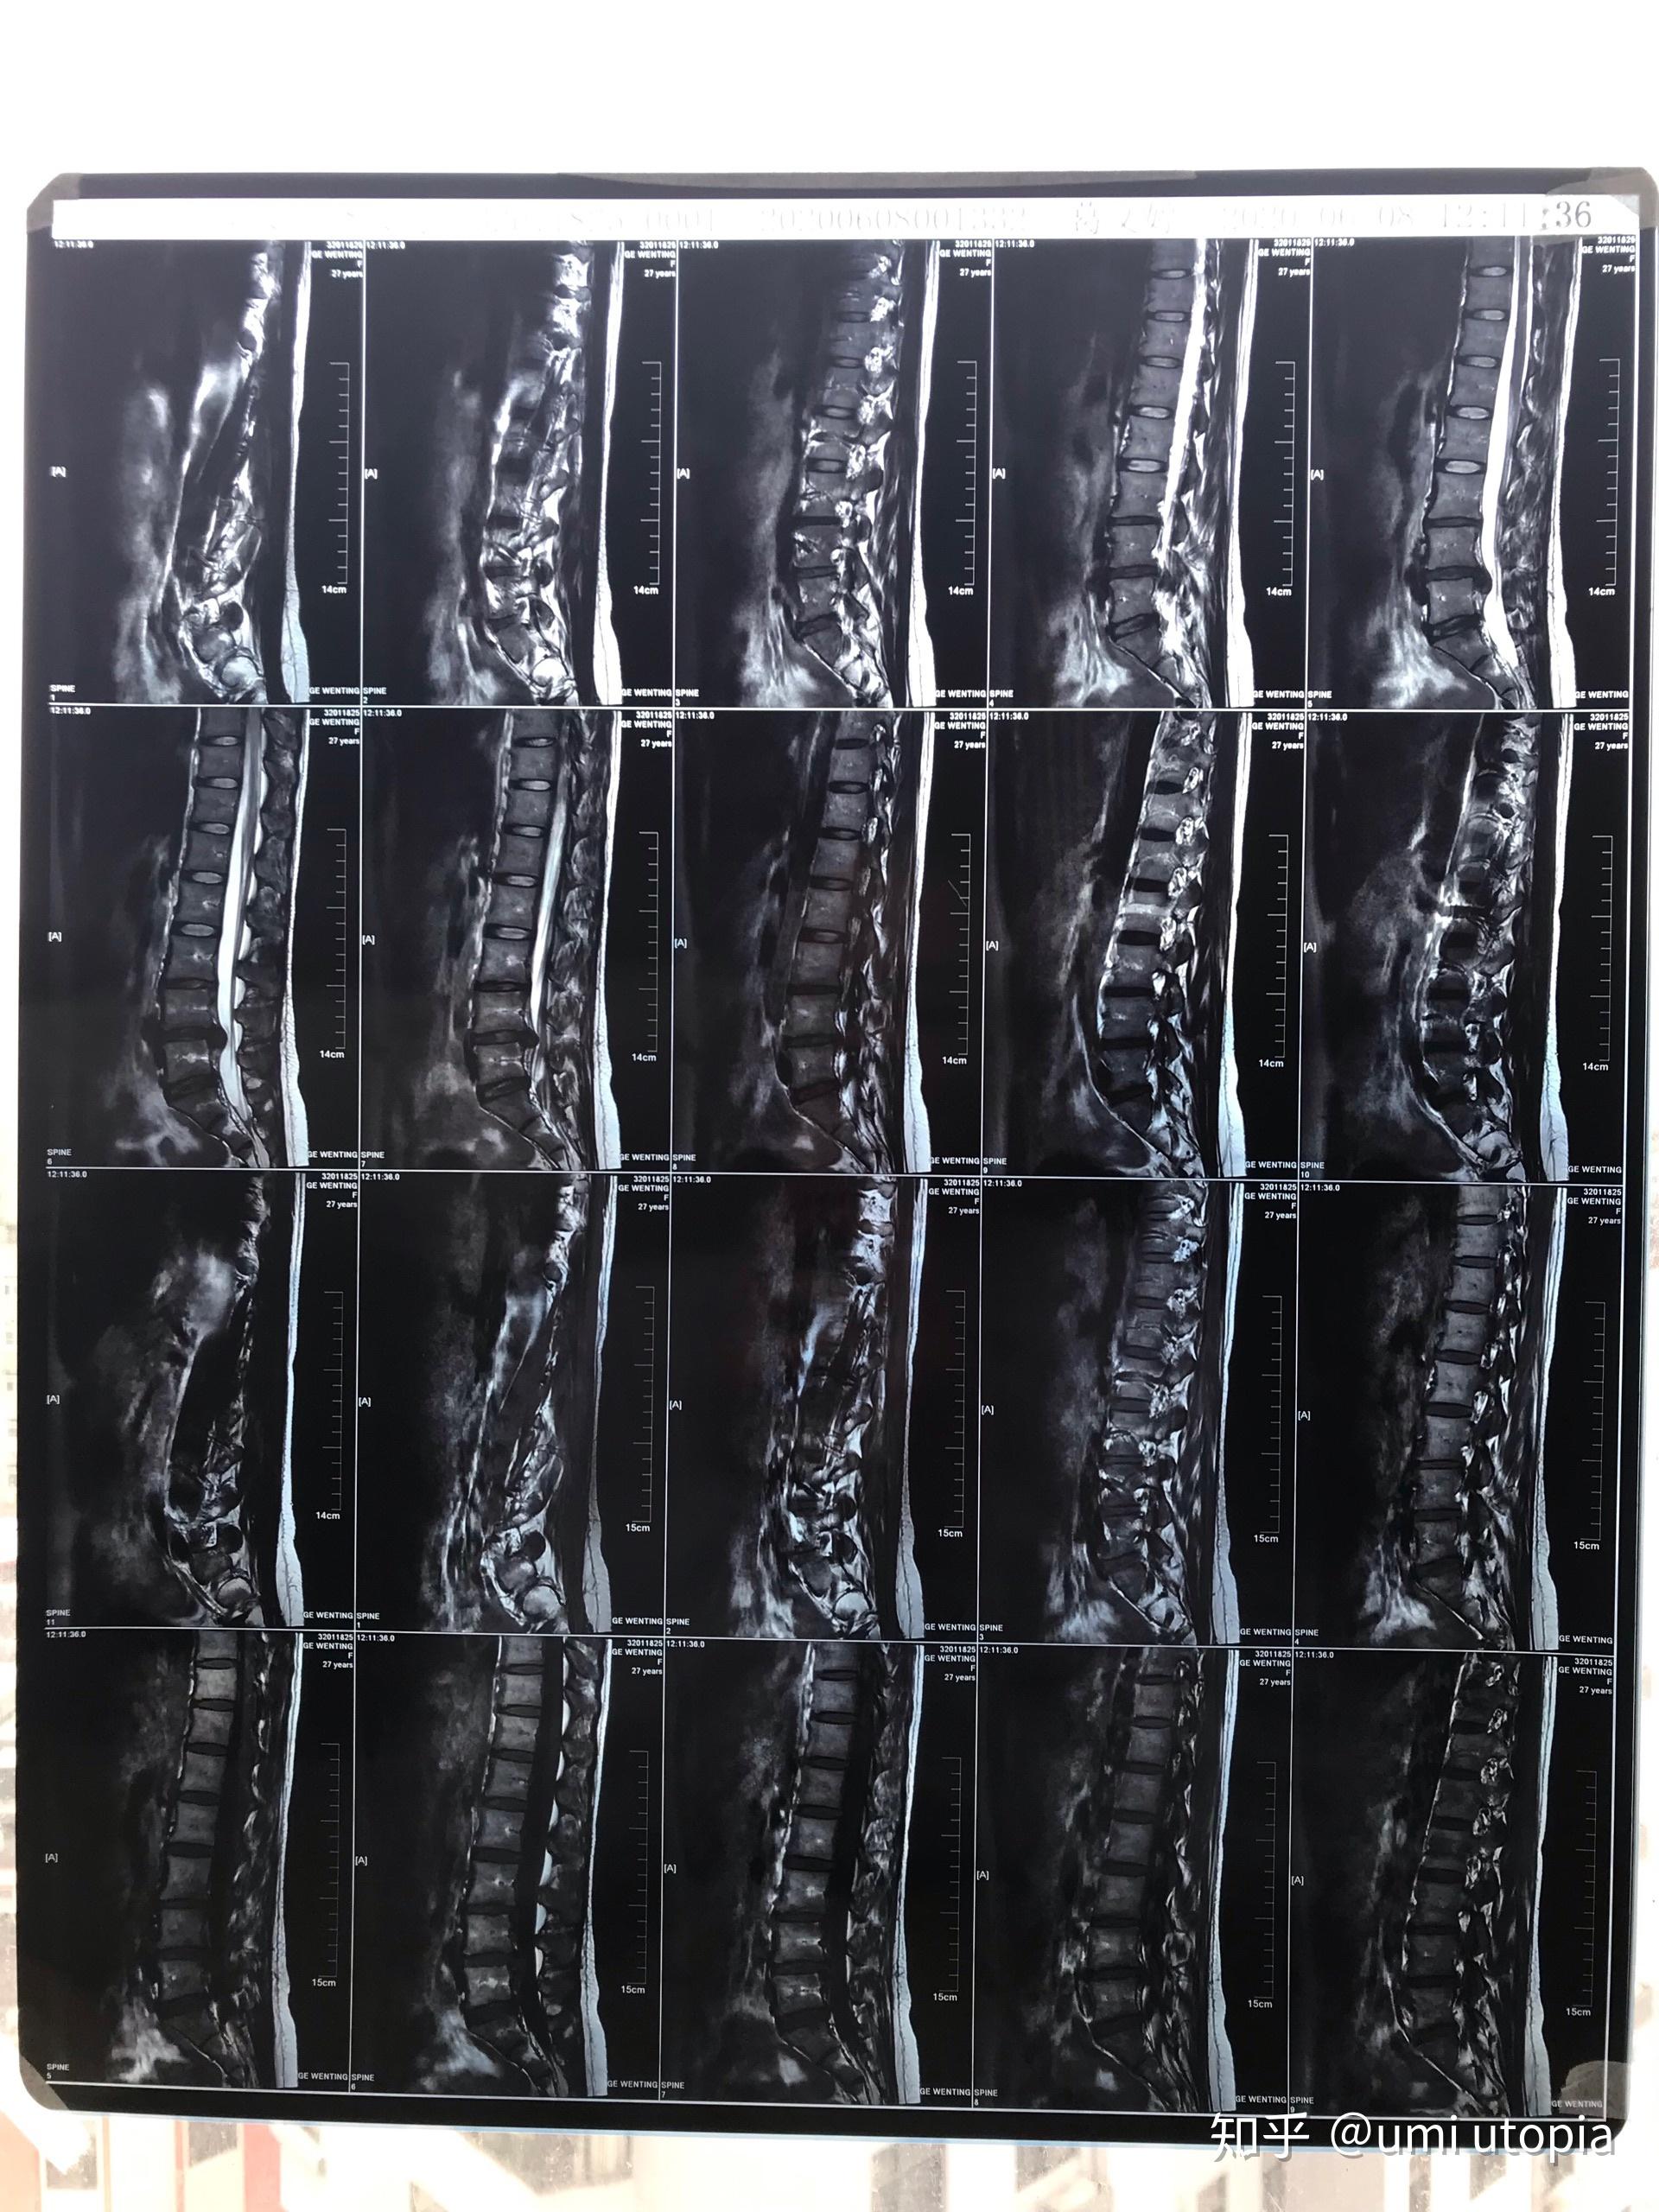

27岁,腰椎间盘l5s1突出压迫右侧神经,附核磁共振,到要手术的程度了吗?

图片尺寸1920x2560

腰椎mri(l5-s1)

图片尺寸2000x2667

核磁共振显示l5_s1椎间盘突出

图片尺寸3456x4608